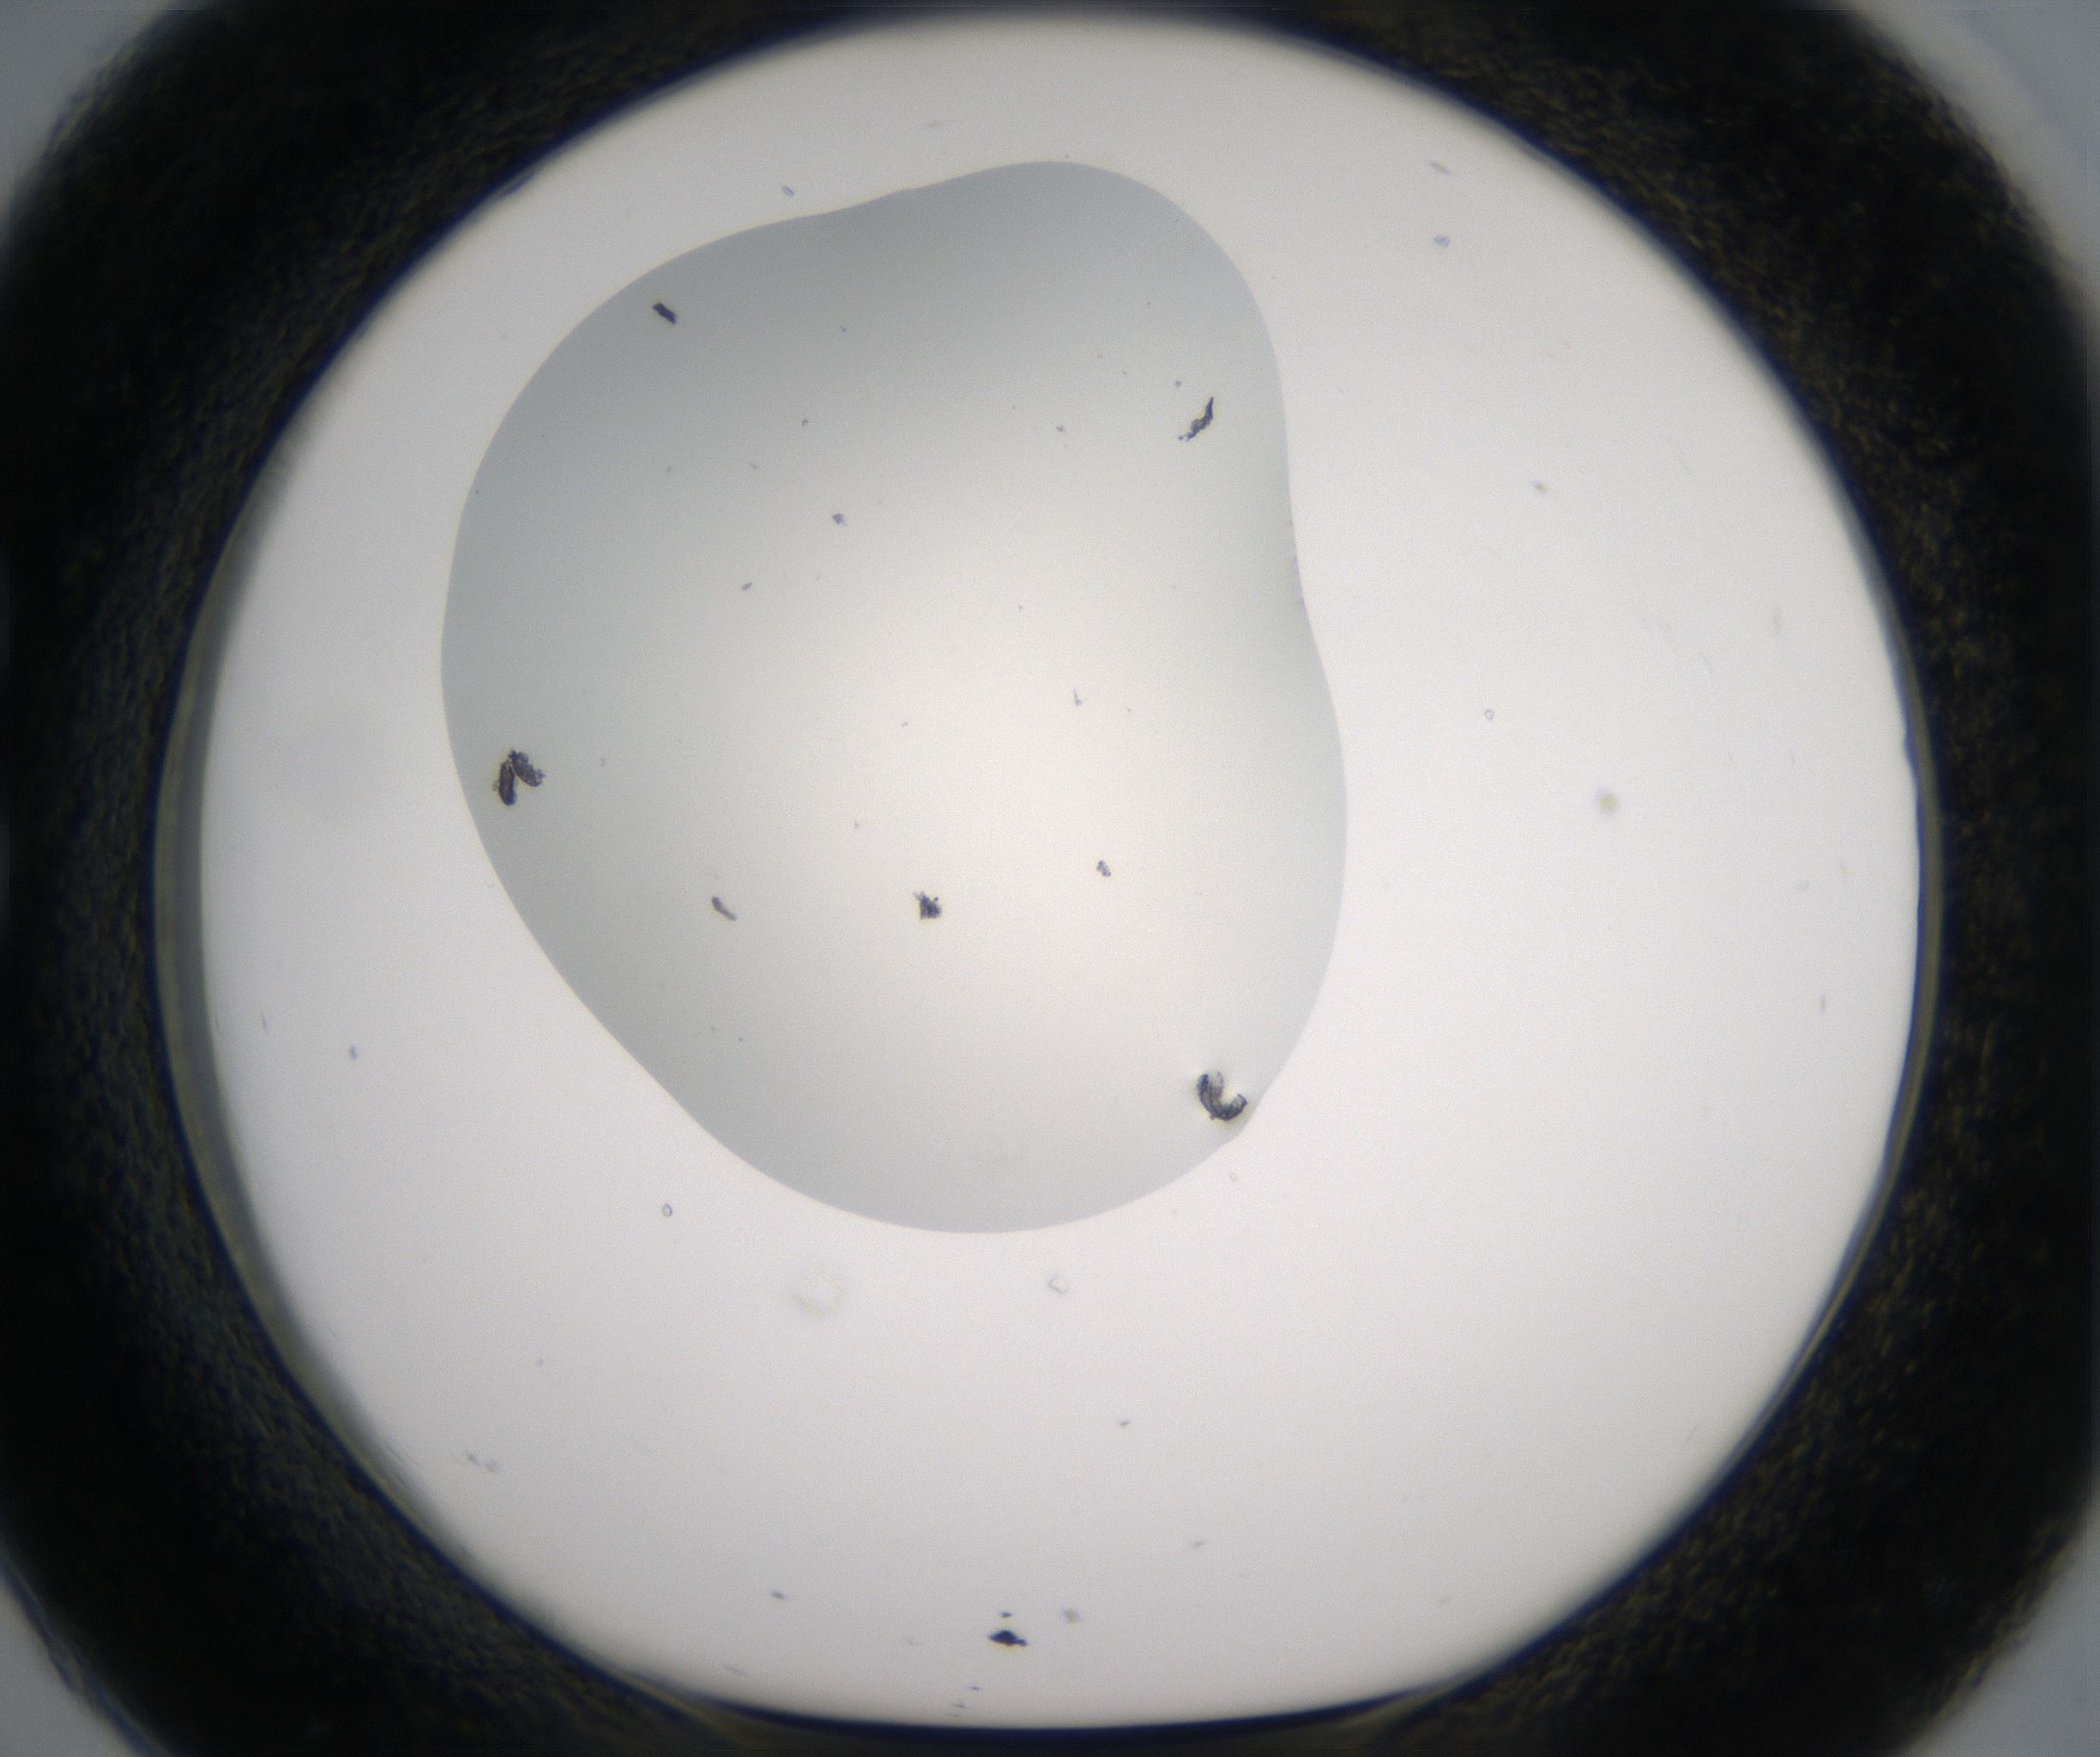

Image 485145

C2_HighResolution_Other_1.jpg